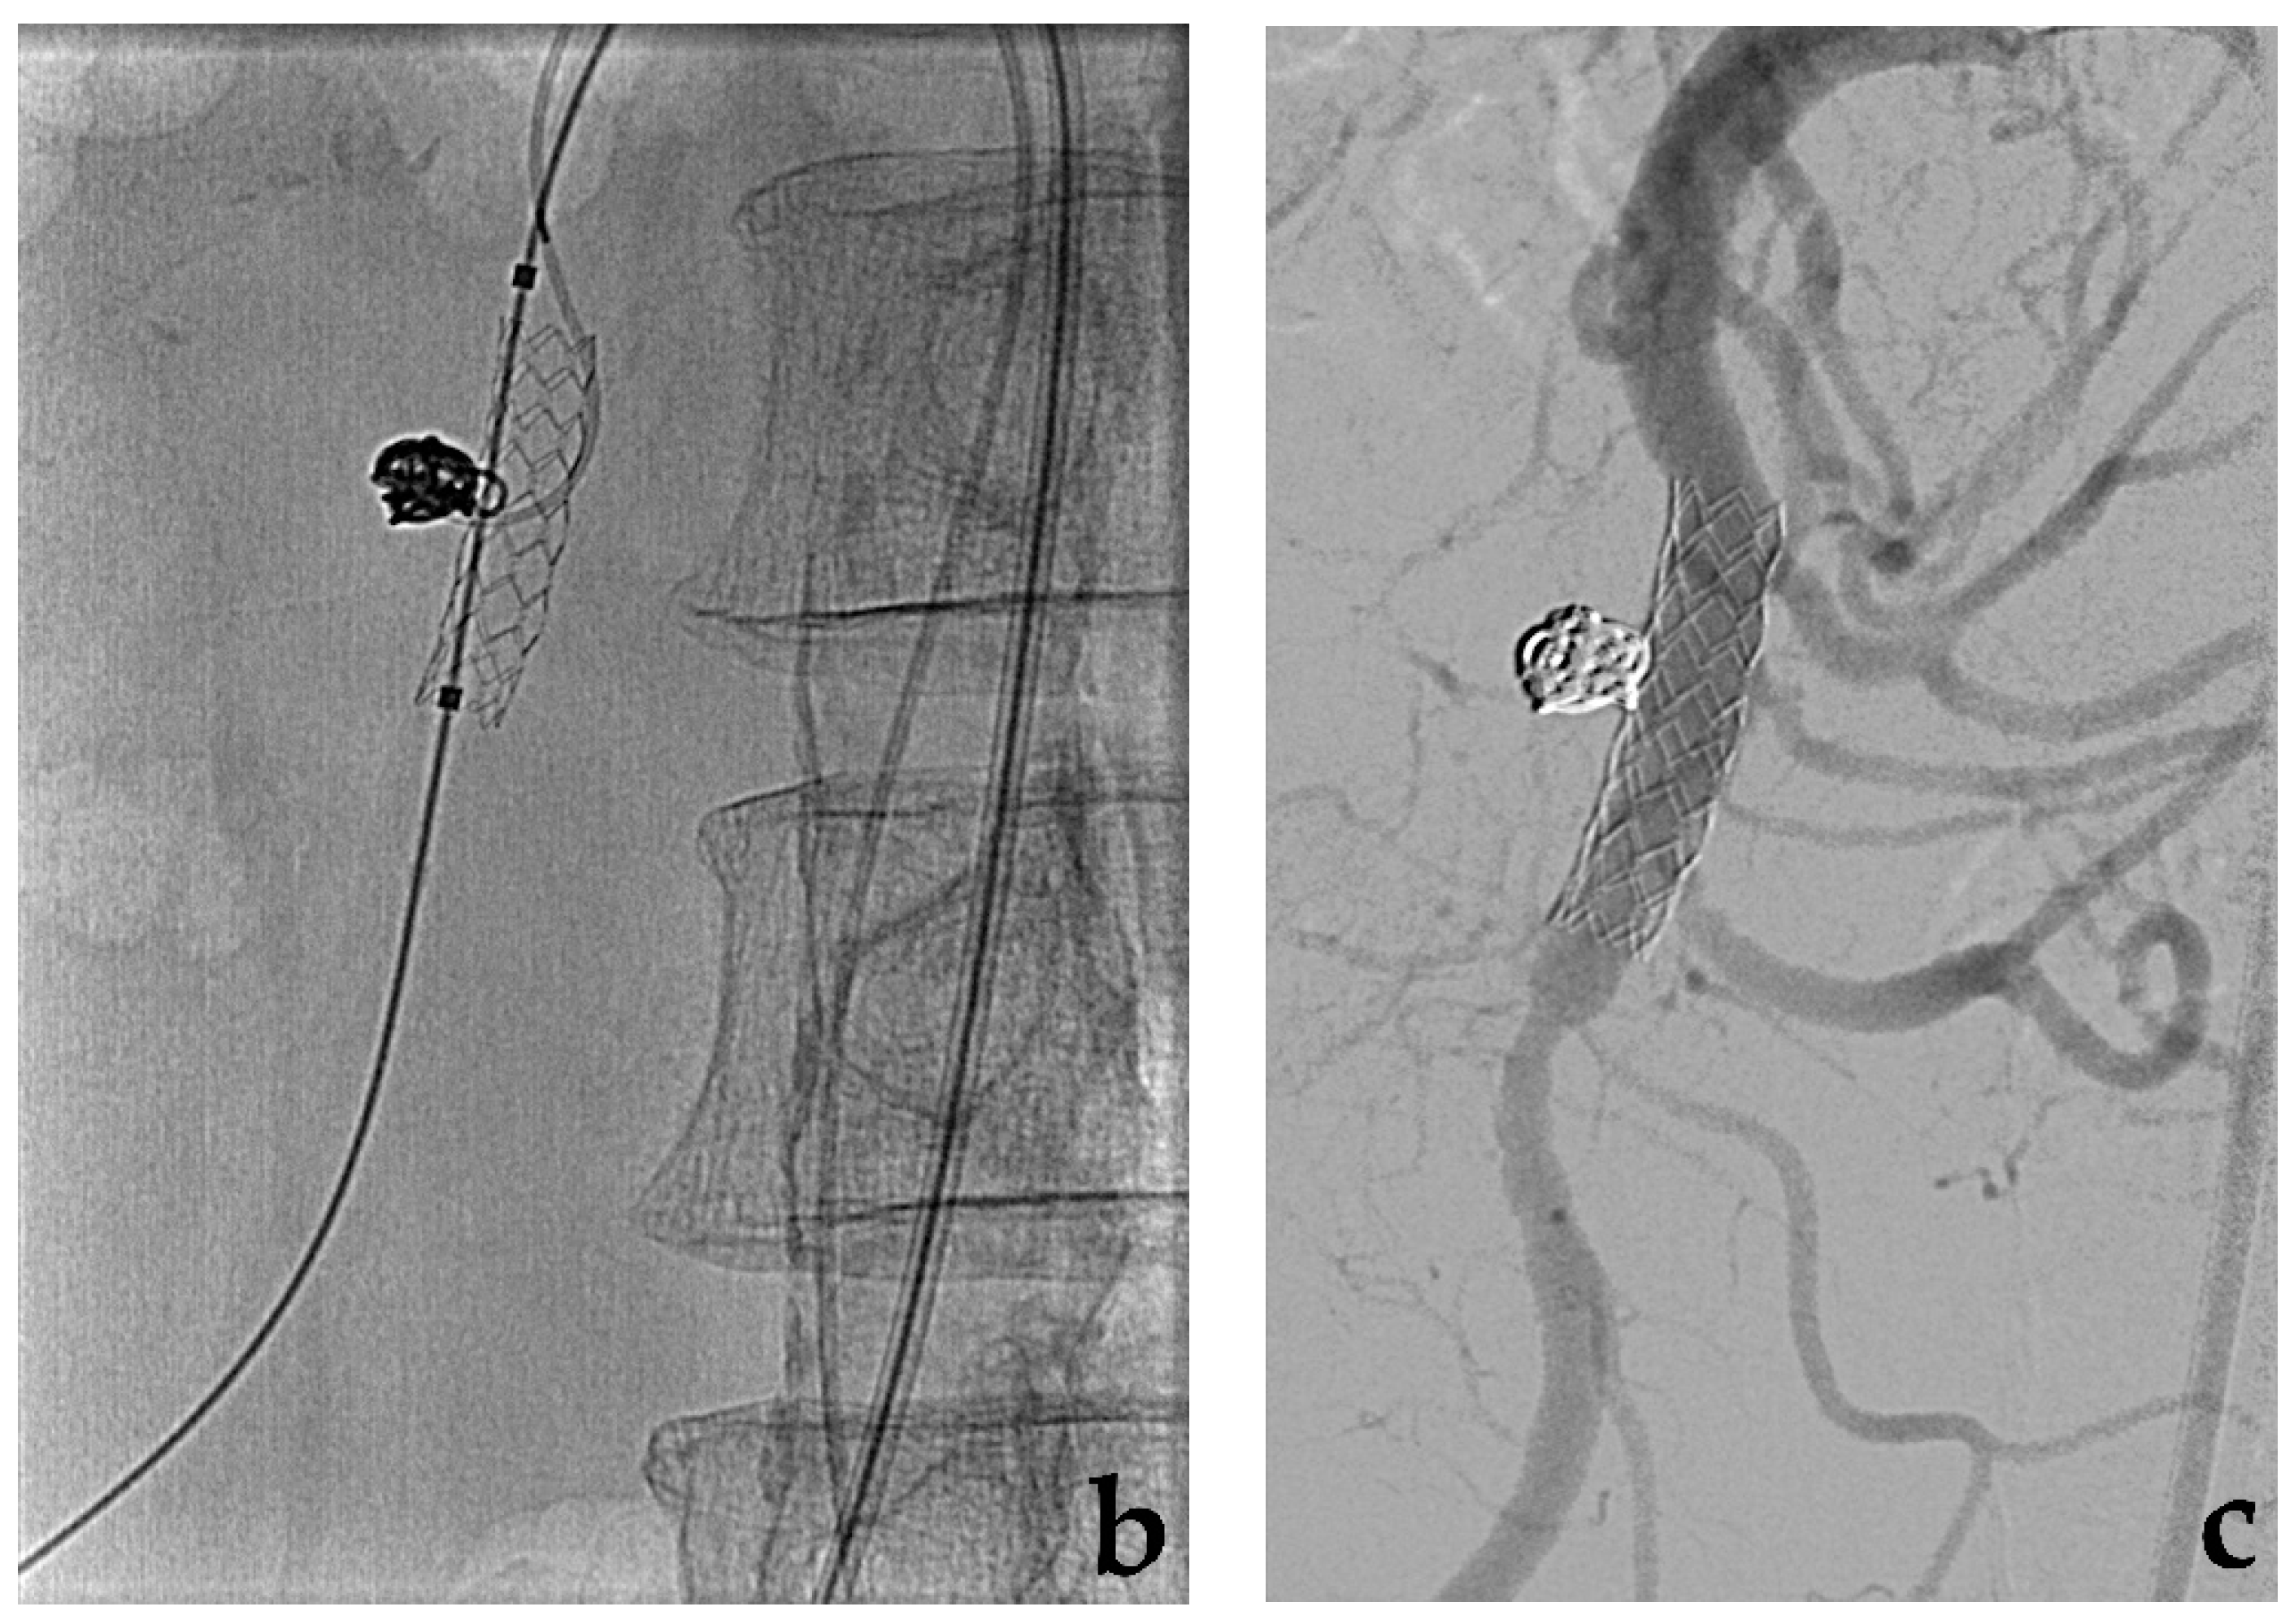

3.2. Stent-Assisted Coil Embolization

- Wei, X.; Sun, Y.; Wu, Y.; Li, Z.; Zhu, J.; Zhao, Z.; Feng, R.; Jing, Z. Management of wide-based renal artery aneurysms using non covered stent-assisted coil embolization. J. Vasc. Surg. 2017, 66, 850–857. [Google Scholar] [CrossRef]

- Secco, G.; Chevallier, O.; Falvo, N.; Guillen, K.; Comby, P.O.; Mousson, C.; Majbri, N.; Midulla, M.; Loffroy, R. Packing technique with or without remodeling for endovascular coil embolization of renal artery aneurysms: Safety, efficacy and mid-term outcomes. J. Clin. Med. 2021, 10, 326. [Google Scholar] [CrossRef]

- Ma, T.; He, Y.; Zhong, W.; Luo, G.; Li, Q.; Wang, Z.; Zhang, H.; Wu, Z.; Qiu, C. Mid-term results of coil embolization alone or stent-assisted coil embolization for renal artery aneurysms. Ann. Vasc. Surg. 2021. [Google Scholar] [CrossRef]

- Bracale, U.M.; Narese, D.; Ficarelli, I.; De Laurentis, M.; Spalla, F.; Dinoto, E.; Vitale, G.; Solari, D.; Bajardi, G.; Pecoraro, F. Stent-assisted detachable coil embolization of wide-necked renal artery aneurysms. Diagn. Interv. Radiol. 2017, 23, 77–80. [Google Scholar] [CrossRef] [PubMed]